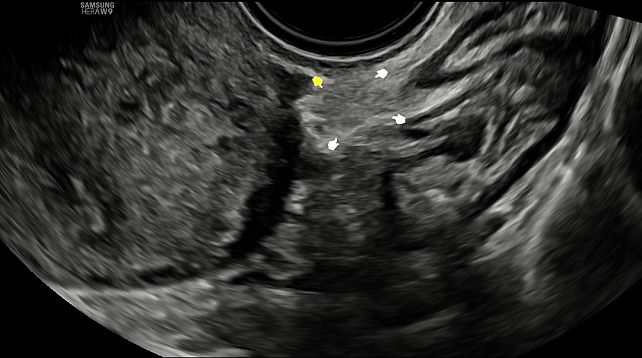

According to the 2025 IDEA addendum, typical sonographic features of SE include: (1) hypoechoic tissue with stromal reaction or fibrosis; (2) hyperechoic foci; (3) cystic areas or vesicles (solitary or clustered, small or large); (4) peritoneal pockets or concave defects; and (5) convex lesions protruding into the peritoneal cavity. These findings may appear alone or in combination, and velamentous (filmy) adhesions can be associated with any of them, although they are not specific (Figure 30, Video 5).6

30

Examples of ultrasound appearance of superficial endometriosis: (A) solitary tiny cyst;

(B) clustered cysts with a honeycomb appearance and associated hypoechoic tissue;

(C) clustered tiny cysts with a linear appearance and associated hypoechoic tissue;

(D) clustered tiny cysts with associated hypoechoic lesions and hyperechoic foci within a peritoneal pocket;

(E) small peritoneal pocket with a hyperechoic focus;

(F) clustered tiny cysts with a honeycomb appearance;

(G) clustered cysts with hyperechoic foci located above a bowel deep endometriotic nodule.

Note, findings may appear in isolation (A,F) or in combination (B,C,D,E,G), and different lesions within the same patient may demonstrate variable associated features.